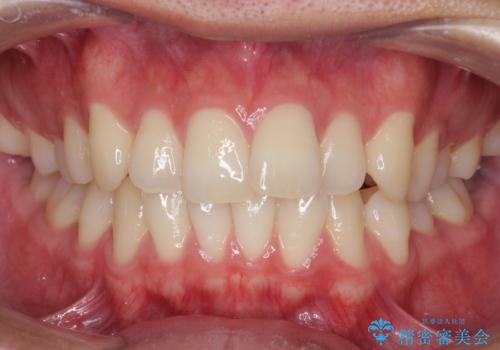

- 患者様

- 20代男性